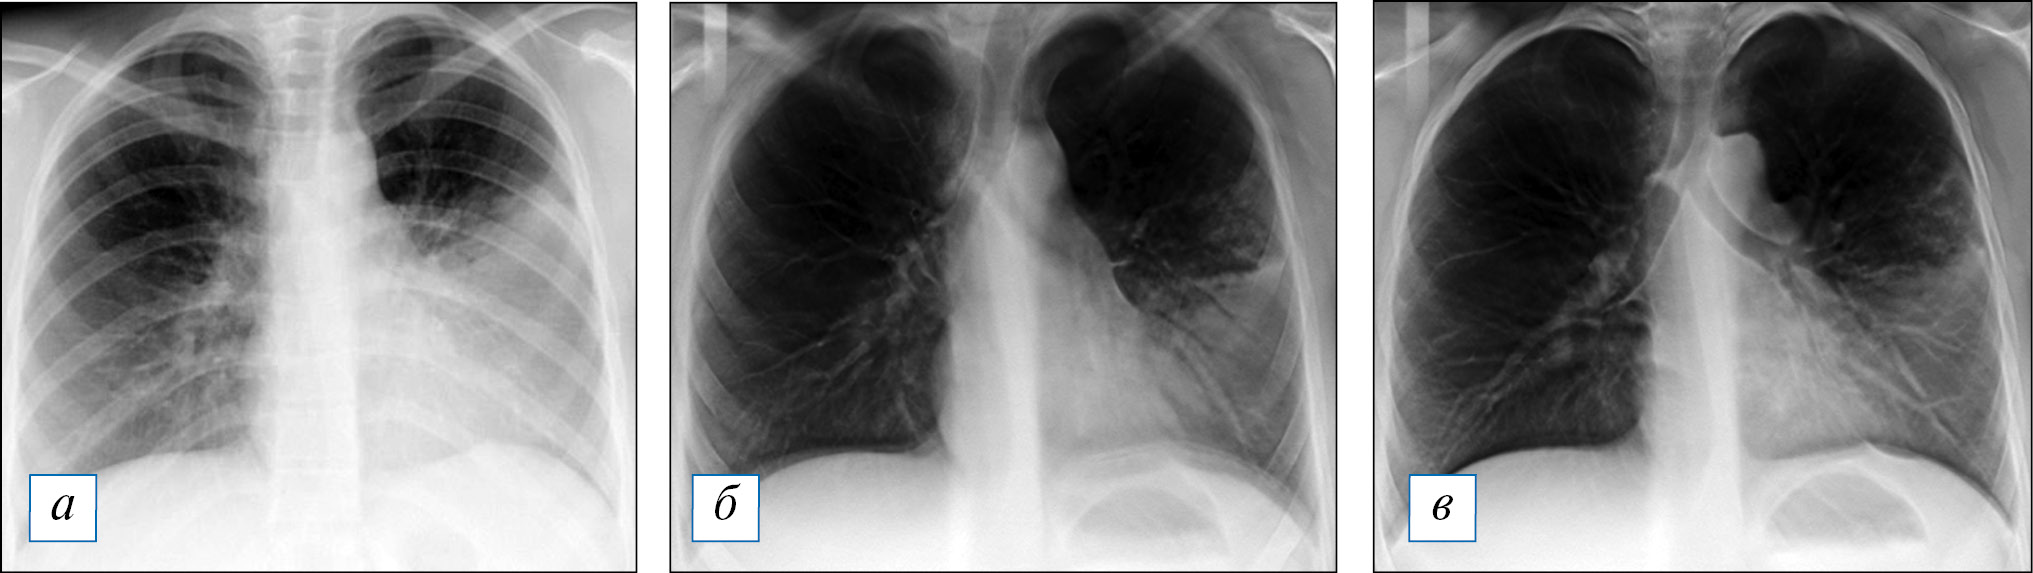

Рис. 3. Результаты проведенного в сопоставимые сроки лучевого обследования пациента Д., 1 год 8 мес, с субтотальной правосторонней деструктивной пневмонией: а — рентгенография; б — томосинтез; в — мультиспиральная компьютерная томография. / Fig. 3. Results of the different examination in comparable periods of the patient D., 1 year 8 months, with subtotal right-sided destructive pneumonia: a — radiography; б — tomosynthesis; в — multispiral computed tomography.